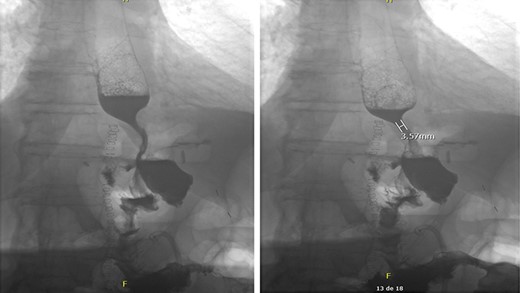

Due to inadequate oral intake and weight loss, an upper gastrointestinal endoscopy was performed 1 year later. An anastomotic stricture was objectified, for which a stent was installed (Fig. 3). The stent was removed 6 weeks later, and the width of the anastomosis was appropriate (Fig. 4).